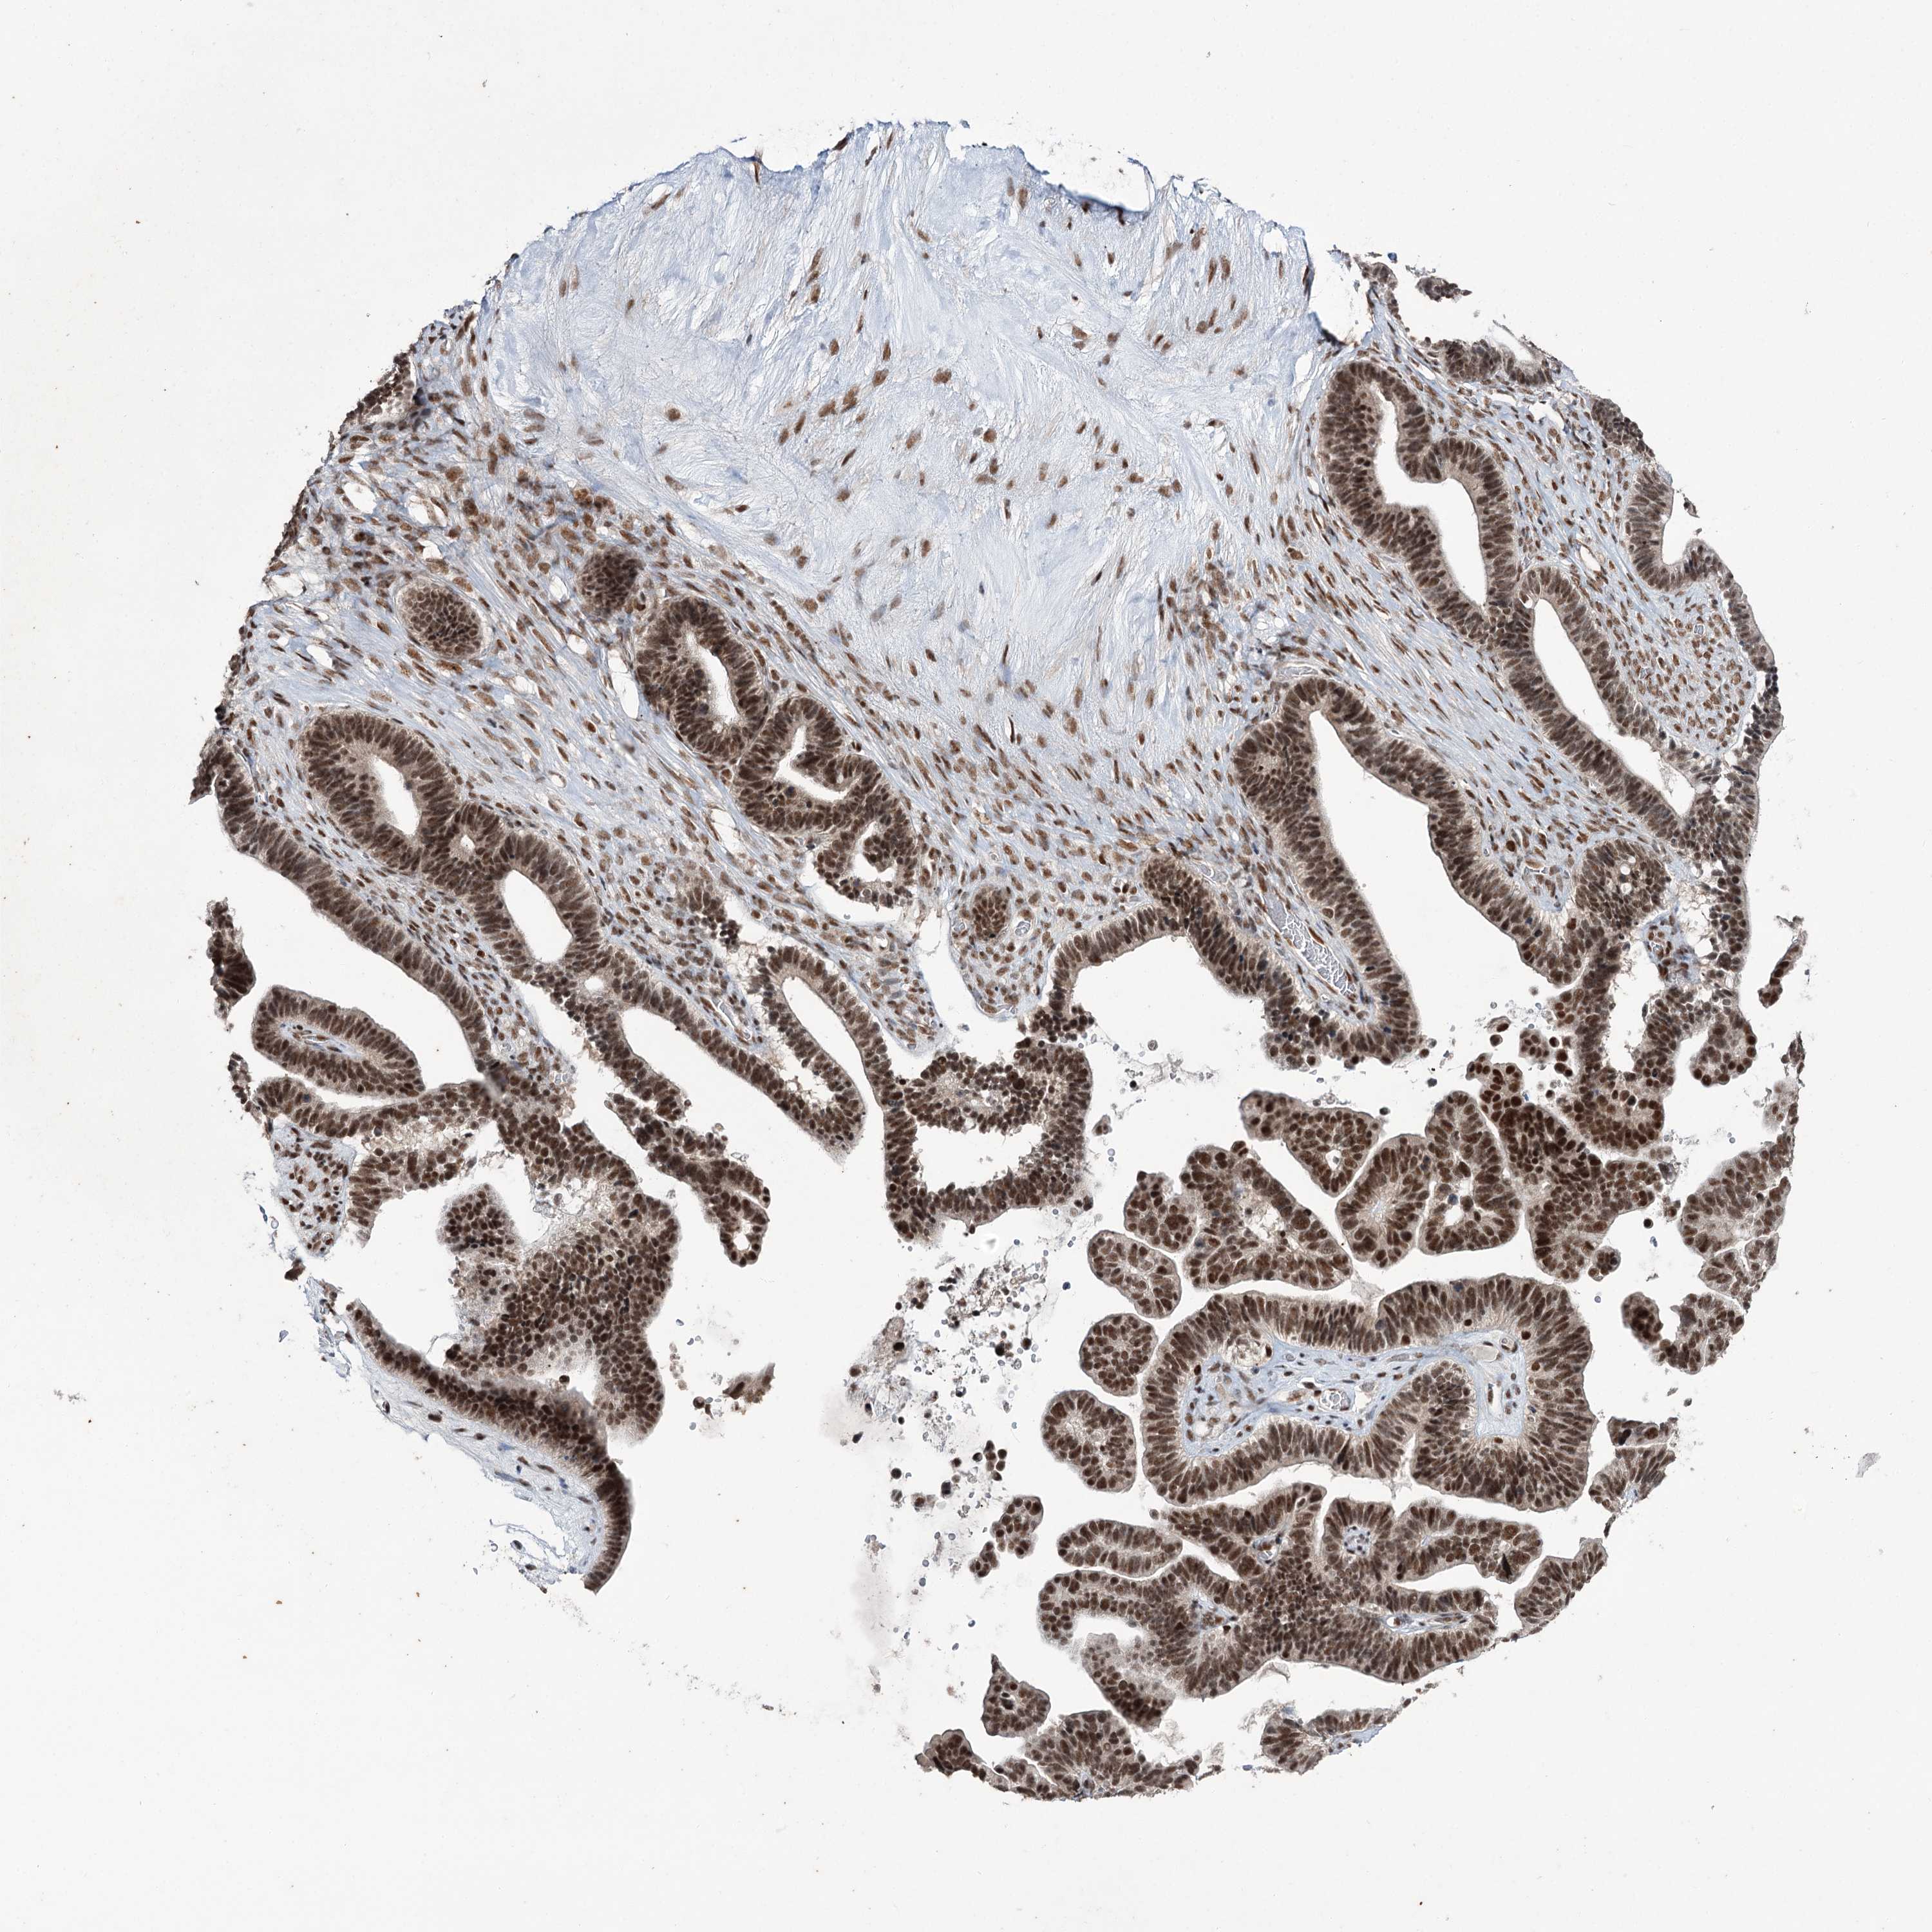

OVARIAN CANCER - Protein expressioni

A mouse-over function shows sample information and annotation data. Click on an image to view it in a full screen mode. Samples can be filtered based on level of antibody staining by selecting one or several of the following categories: high, medium, low and not detected. The assay and annotation is described here.

Note that samples used for immunohistochemistry by the Human Protein Atlas do not correspond to samples in the TCGA dataset.

Antibody stainingi

Antibody staining in the annotated cell types in the current human tissue is reported as not detected, low, medium, or high, based on conventional immunohistochemistry profiling in selected tissues. This score is based on the combination of the staining intensity and fraction of stained cells.

Each image is clickable and will lead to virtual microscopy that enables deeper exploration of all samples and also displays staining intensity scores, fraction scores and subcellular localization as well as patient and tissue information for each sample.

Antibody CAB037153

Cystadenocarcinoma, serous, NOS

Carcinoma, endometroid

Cystadenocarcinoma, mucinous, NOS

Carcinoma, NOS